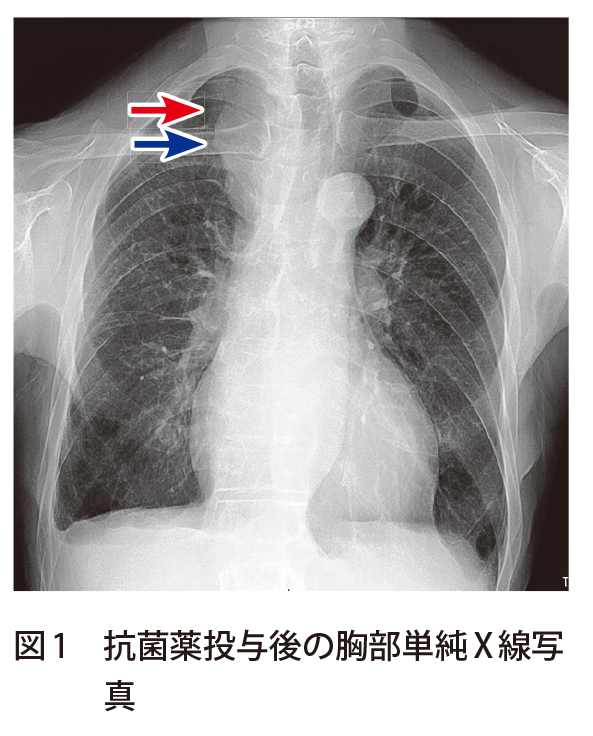

鎖骨下静脈〜左上肢中枢にかけての狭窄疑いとして,ct検査がオーダされ,画像診断科医師の要望により,(1) 単純,(2) 動脈相,(3) 静脈相で撮影を行った。 所 見左鎖骨下静脈は左第1肋骨と接しており,同部位で50%程度の狭窄を認める。に十分なct 値が得られ、pvpa の平均ct 値 差は分離可能なct 値差が得られている結果 となった。 fig1 pa とpv、pvpa のct 値 考察・結語 再考した1 相撮影において、肺動静脈ともにvr 作成に十分なct 値を保ちつつ、分離可能なct 値差左上腕:27 cm,左前腕:265 cmと右上肢の腫脹と皮下 静脈の怒張を認めた。 術前胸部造影CT 像(Fig 1A,B):冠状断像では右腕頭 静脈から分岐した右鎖骨下静脈が起始部から血栓閉塞し ているのが確認され,水平断像では右上腕の皮下静脈の 怒張を認めた。

左鎖骨下静脈およびその中枢静脈の狭窄の有無および, 外頸静脈へのバイパス作成による, 静脈系の減圧の可能性を確認するため, 静脈造影検査, および造影CT検査を行った鎖骨下静脈には狭窄, 血栓の所見はなく, さらに鎖骨下静脈と内頸静脈との合流部鎖骨下静脈(SV)の局所解剖(図2)7) 腋窩静脈(axillary vein,AV)は上腕静脈に続いて腋窩 部より起始し,肋骨前方で大胸筋後方に腋窩動脈と並 走する。腋窩三角に存在するこの区間では,皮下から 静脈に至る経路は深く,大胸筋と小胸筋により成る2 (211 中心静脈栄養の選択ルートはいくつかありますが、 内頸静脈や、鎖骨下静脈、下大総腸骨静脈などのルートは右側からが多いですよね。 そのことに疑問を投げかけてきた人がいまして、ちょうどいい機会なので調べてみました。 左からさすと胸管損傷をおこすからというおおざっぱな理由